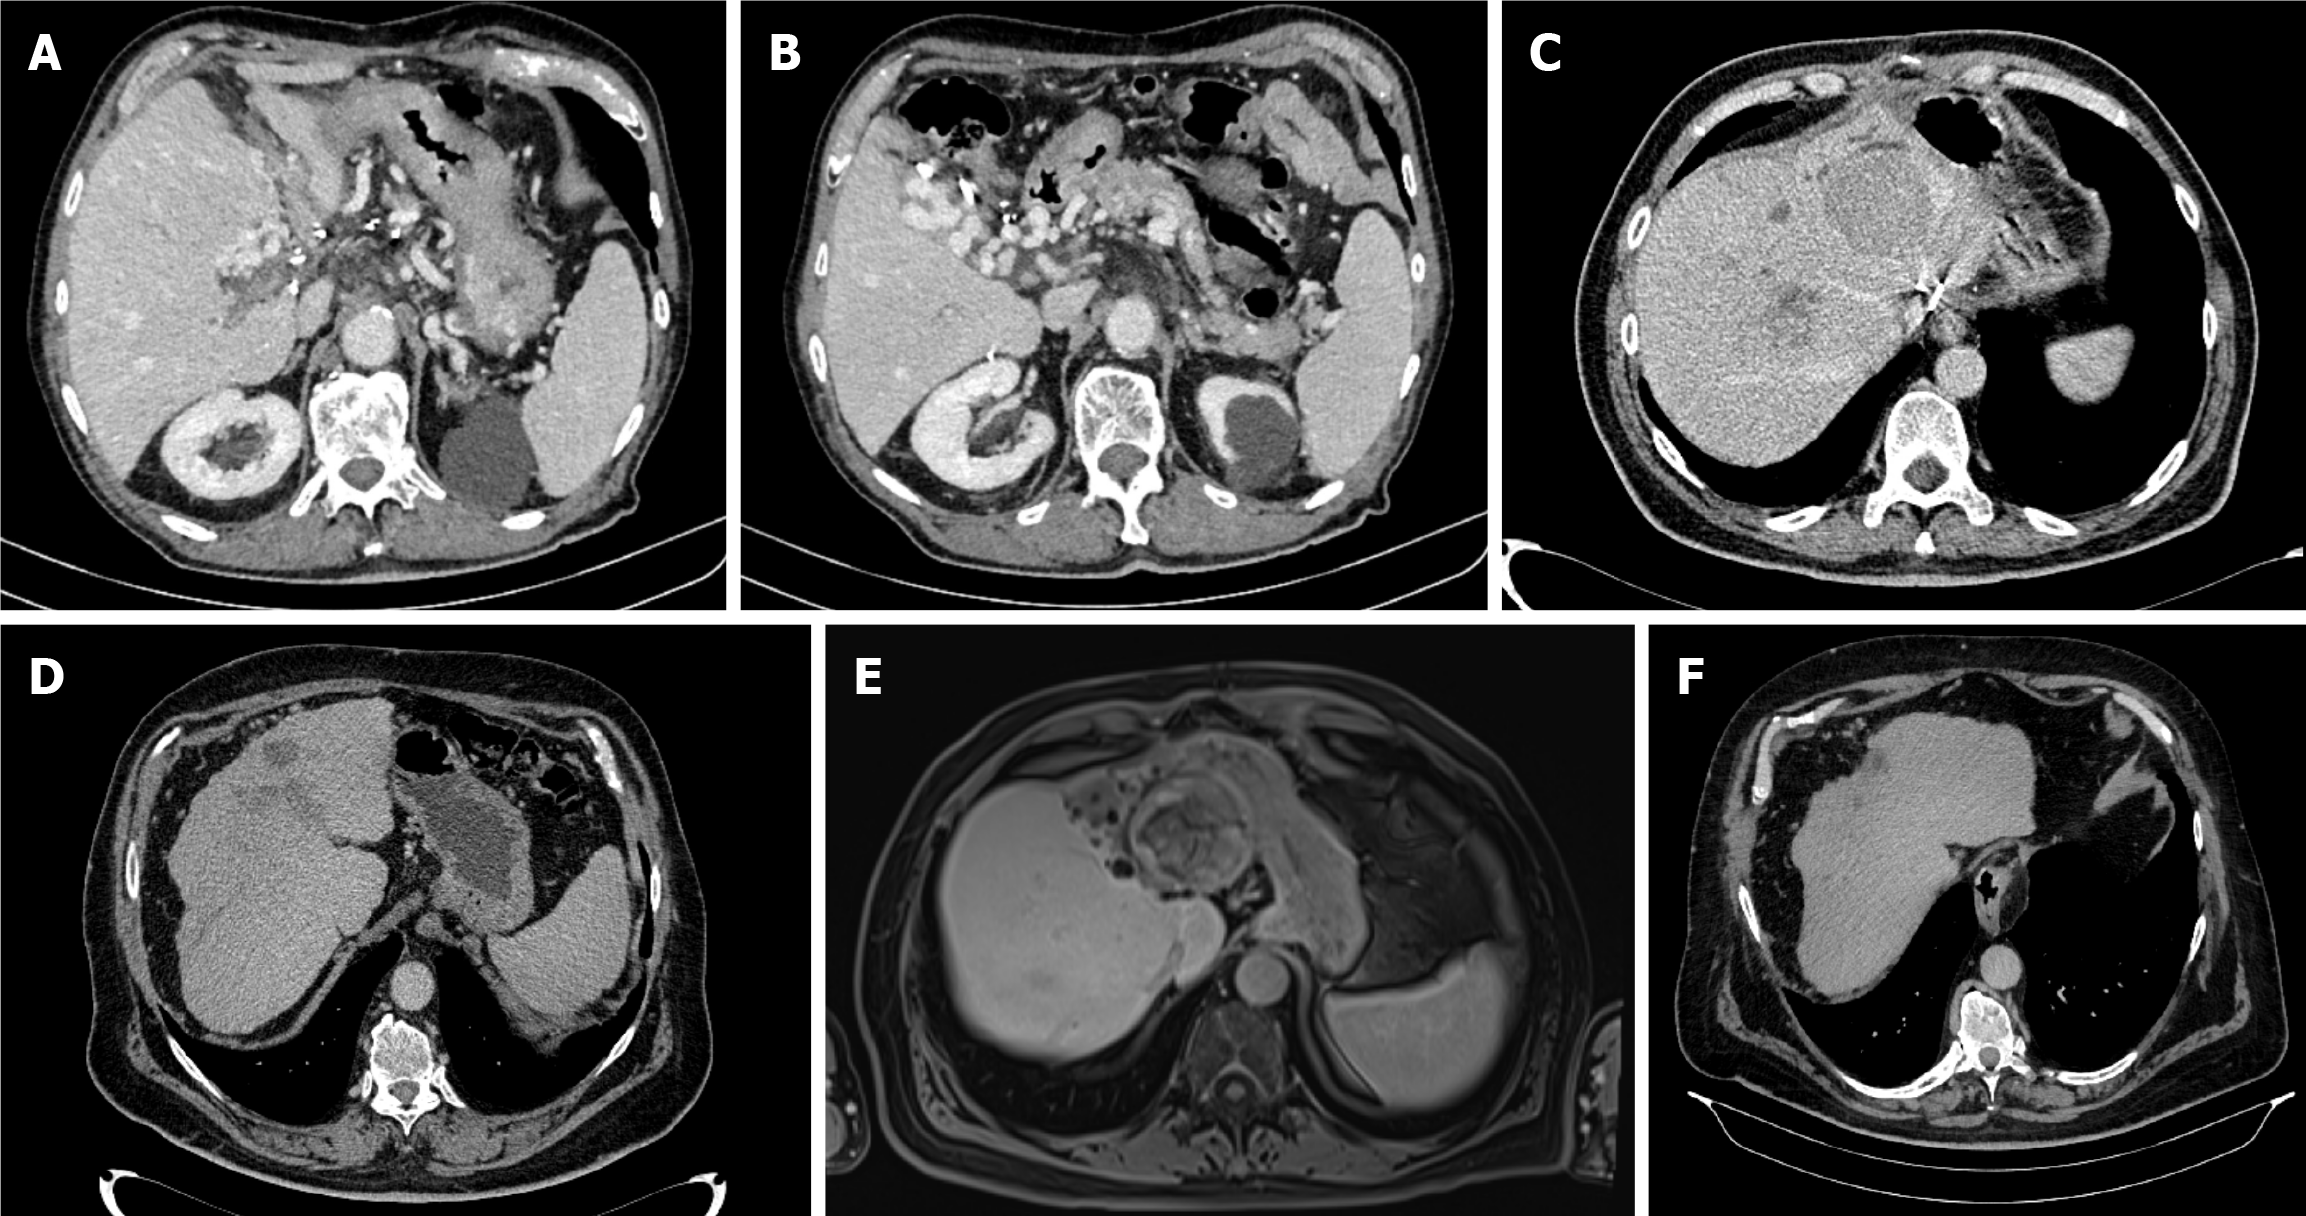

Case 3: Further workup, which included a multislice CT scan of the thorax, abdomen, and pelvis, identified a 7-cm mass in the liver’s caudate lobe, accompanied by portal and splenic vein thrombosis (Figure 1A and B). Magnetic resonance imaging (MRI) of the abdomen showed no additional lesions. Due to the lesion’s proximity to major vascular structures, a biopsy was not performed.

An MRI scan in March 2024 showed that the largest lesion in liver segment III was 55 mm. This area, along with all of the other lesions, appeared to have undergone complete necrosis with no viable tumor cells found (Figure 1E). The patient was re-evaluated by the MDT as a potential liver transplantation candidate; however, the procedure was deemed sur

The patient’s treatment continued until October 2024, but was subsequently paused and ultimately discontinued due to the development of grade 2 thrombocytopenia per CTCAE. A follow-up PET-CT scan conducted in October 2024 revealed no evidence of metabolically active lesions. The last imaging follow-up was a CT scan in April 2025, which showed no signs of a viable tumor, and the AFP value was 2 ng/mL (Figure 1F).